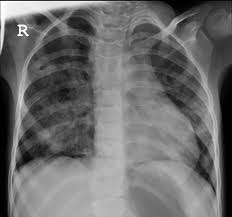

Pneumonia Acute Inflammation Of The Lung Parenchyma The

Pneumonia Acute Inflammation Of The Lung Parenchyma The from s2.studylib.net

Lung parenchyma is the substance of the lung that is involved with gas exchange and includes the pulmonary alveoli and respiratory bronchioles, though some authors include only the alveoli. Bird fancier's lung (avian proteins) is most common in children! An umbrella term that encompasses a large number of disorders that are characterised by diffuse cellular infiltrates in a periacinar location. Patients usually respond to removal of antigen. The lung parenchyma is further subdivided. The closest locations of metastases of the primary lesions are in the peritoneum and bowels 7, 8. In general, squamous carcinomas are encountered. If a large enough segment of parenchyma is involved, it can alter the transmission of air and sound. Most lung nodules are benign (not cancerous). Parenchyma in the lungs essentially includes all systems and tissues pertinent to the lung's healthy functioning. Infected lung parenchyma can affect a person's breathing. Pneumonia is an infection of the lung parenchyma caused by a wide variety of organisms in pediatric patients. The lung parenchyma is that portion of the lungs involved in gas exchange.

Respiratory area of the lungs (lung parenchyma) the structures in the lungs directly responsible for the function of respiration collectively form the lung parenchyma. Consolidation occurs when the normally air filled lung parenchyma becomes engorged with fluid or tissue, most commonly in the setting of pneumonia. Each alveolus in the lung parenchyma opens directly into an alveolar duct or occasionally, in a limited number of species, into a respiratory bronchiole. Diffuse parenchymal lung diseases are disorders that affect the interstitial of the lungthe area around the lung's air sacs. Interstitial lung disease seems to occur when an injury to your lungs triggers an abnormal healing response. It includes the bronchial tubes, blood vessels, alveoli, and alveolar ducts 31, 32. Lung parenchyma, however, more extensively involves the bronchioles or lung airways, as well as key blood vessels located inside of the lungs. The most accurate way to determine if a lung disease affects this part of the lung is with a surgical biopsy.